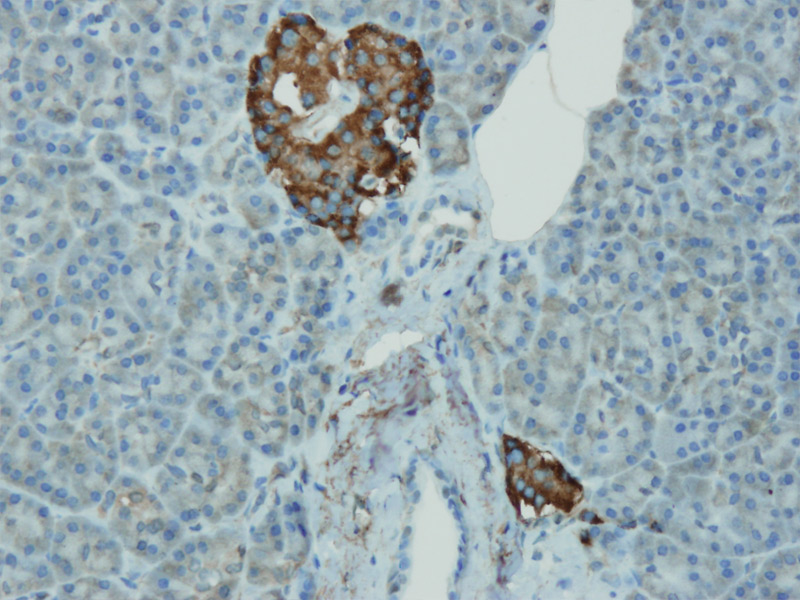

Anti-Chromogranin A

Rabbit clonal antibody

Product ID:DB 158 Category:IHC-P

IHC-P, dilution 1:100

db158